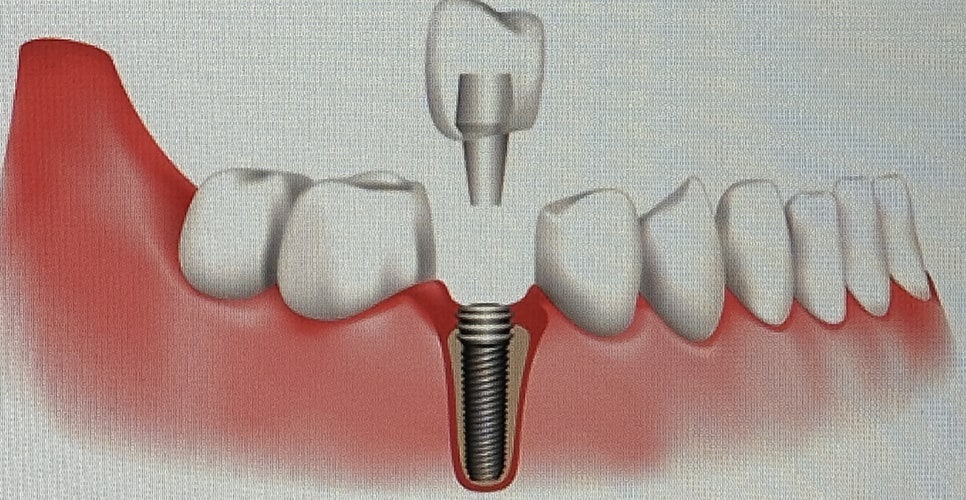

이 치료는 상실된 치아를 대체하여

저작, 발음, 연하 기능을 수행할 수 있도록

치조골에 픽스처(Fixture)를 식립하고

인공치를 만드는 수술을 얘기합니다.